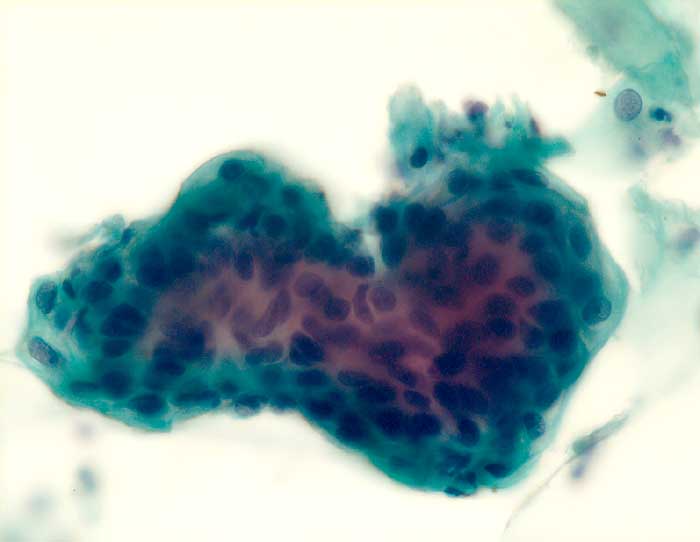

Die Zellkerne der serösen Adenokarzinome sind in den meisten Fällen hochgradig atypisch. Das Zellbild gleicht entsprechend demjenigen eines wenig differenzierten endometrioiden Adenokarzinoms. Da das seröse Karzinom anders als das endometrioide Karzinom nicht Folge eines Hyperöstrogenismus ist, zeigen die meist postmenopausalen Patientinnen keinen hohen Aufbau des Vaginalepithels im PC-Abstrich.